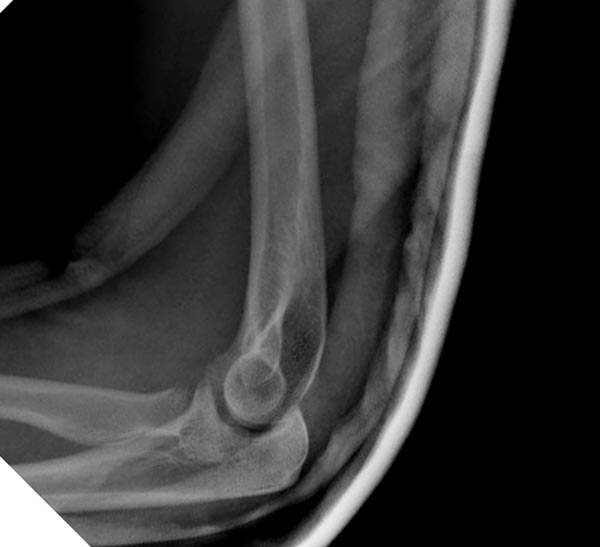

Вместе обычных простых рентгенограм, участились злоупотребления дорогими исследованиями. Хотя многие переломы, даже внутрисуставные, можно увидеть на обычных рентген снимках. Негативный рентген при исследовании локтевого сустава не означает отсутствие перелома. Если имеется “fat pad sign”, характерный симптом для внутрисуставных повреждений, тогда можно ставить диагноз перелом головки луча! Гематома внутрисуставного перелома смещает жировое тело и на боковом снимке проявляется в виде “паруса”.

Для выработки показаний достаточным бывают стандартные снимки, но иногда требуется косая рентгенограмма по Coyle. И для подтверждения смещений и оценки внутрисуставных фрагментов рекомендуется КТ, а 3D снимки показывают только поверхность, т.е. получается общая картина. МРТ дает возможность оценить состоянии связок.

В первом случае перелом Монтеджи, где доперационно сделано оценка положения головки к остальным элементам под рентгеном. Учитывая правильность взаимотношении произведена фиксация только локтевого отростка, Второй случай, заменена на протез, и третий, кроме фиксации головки - реконструкция capitellum латерального мыщелка.